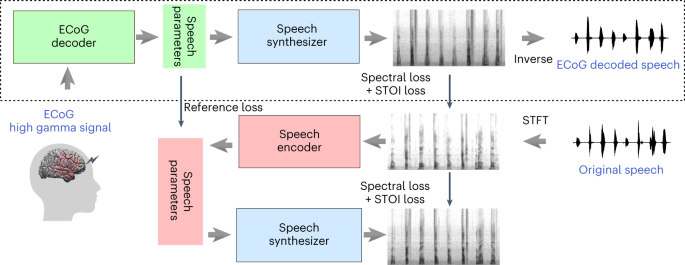

2 Model Architecture

Following [ 9 ] , the proposed system consists of three components: a speaker encoder , which computes a fixed-dimensional embedding vector from a few seconds of reference speech of a target speaker; a synthesizer , which predicts a mel spetrogram from an input text and an embedding vector; a neural vocoder , which infers time-domain waveforms from the mel spectrograms generated by the synthesizer. At inference time, the speaker encoder takes as input a short reference utterance of the target speaker and generates, according to its internal learned speaker characteristics space, an embedding vector. The synthesizer takes as input a phoneme (or grapheme) sequence and generates a mel spectrogram, conditioned by the speaker encoder embedding vector. Finally the vocoder takes the output of the synthesizer and generates the speech waveform. This is illustrated in Figure 1 .

2.3 Synthesizer and Vocoder

The synthesizer component of the system is a sequence-to-sequence model with attention [ 1 , 3 ] which is trained on pairs of text derived token sequences and audio derived mel spectrogram sequences. Furthermore, the network is trained in a transfer learning configuration (see Paragraph 2.4 ), using an independently-trained speaker encoder to extract embedding vectors useful to condition the outcomes of this component. In view of reproducibility, the adopted vocoder component of the system is a Pytorch github implementation 1 1 1 https://github.com/fatchord/WaveRNN of the neural vocoder WaveRNN [ 15 ] . This model is not directly conditioned on the output of the speaker encoder but just on the input mel spectrogram. The multi-speaker vocoder is simply trained by using data from many speakers (see Section 3 ).

2.4 Transfer Learning Modality

The conditioning of the synthesizer via speaker encoder is the fundamental part that makes the system multi-speaker: the embedding vectors computed by the speaker encoder allow the conditioning of the mel spectrograms generated by the synthesizer so that they can incorporate the new speaker voice. In [ 9 ] , the embedding vectors are speaker embeddings obtained by Equation 2 . We used the utterance embeddings computed by Equation 1 . In fact, at inference time only one utterance of the target speaker is fed to the speaker encoder which therefore produces a single utterance-level d-vector. Thus, in this case, it is not possible to create an embedding at the speaker level since the average operation cannot be applied. This implies that only utterance embeddings can be used during the inference phase. In addition, an average mechanism could cause some loss in terms of accuracy. This is due to larger variations in pitch and voice quality often occurring in utterances of the same speaker while utterances have lower intra-variation. Following [ 9 ] , the embedding vectors computed by the speaker encoder are concatenated only with the synthesizer encoder output in order to condition the synthesis. However, we experimented with a new concatenation technique: first we passed the embedding through a single linear layer and then we applied the concatenation between the output of this layer and the synthesizer encoder one. The goal was to exploit the weights of the linear layer to make the embedding vector more meaningful, since the layer was trained together with the synthesizer. We noticed that this method achieved good convergence of training and was about 75% times faster than the former vector concatenation.